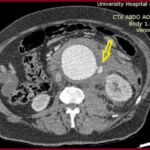

Ανεύρυσμα κοιλιακής αορτής-Ανοιχτή Αποκατάσταση

Η ανοιχτή αποκατάσταση ανευρύσματος κοιλιακής αορτής είναι χειρουργική επέμβαση κατά την οποία το παθολογικά διατεταμένο τμήμα της αορτής αντικαθίσταται με συνθετικό αγγειακό μόσχευμα για την αποκατάσταση της φυσιολογικής ροής του αίματος.